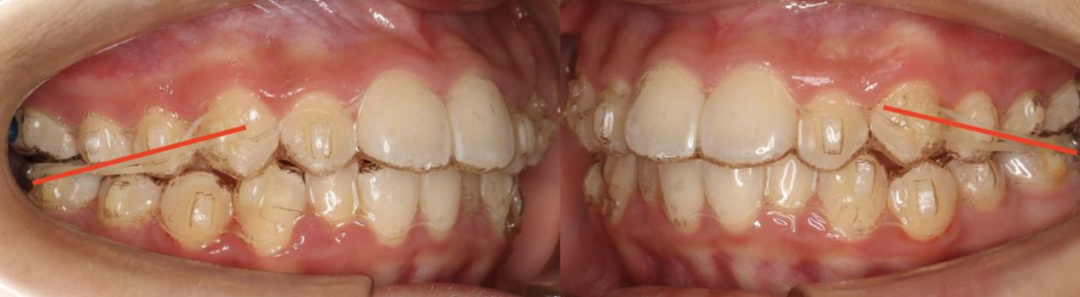

II类下颌后缩的矫治关键点是三个:

(1)上前牙压低,控制转矩内收,为下颌逆时针旋转生长创造空间。

(2)下前牙压低,直立内收,创造前牙咬合的覆盖,上下前牙之间的水平向和垂直向的距离是下颌逆时针旋转生长的空间。

(3)整平下颌后部Spee曲线,是通过咬合引导下颌逆时针旋转生长的关键。